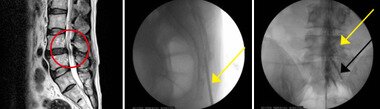

본문 이미지 - 신경이 지나는 통로가 좁아져 있는 모습(첫번째)과 병소 부위(두번째), 다리쪽으로신경관 (노란색)이 유착된 사진(세번째)© News1

신경이 지나는 통로가 좁아져 있는 모습(첫번째)과 병소 부위(두번째), 다리쪽으로신경관 (노란색)이 유착된 사진(세번째)© News1